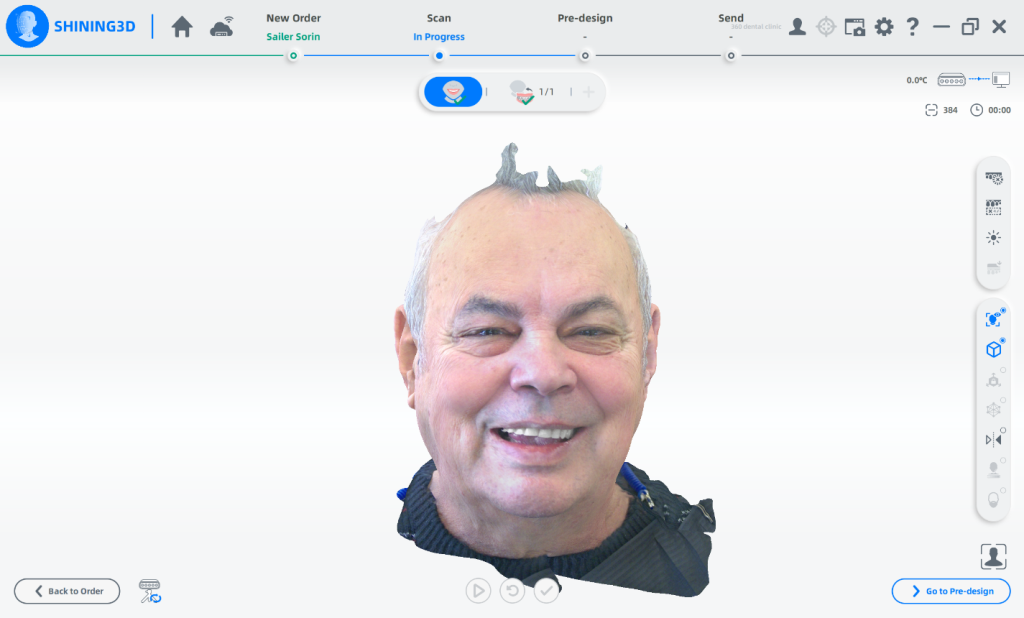

To prepare for the maxillary all on X procedure patient had the upper denture relined with impression material and also multiple dots of radio opaque filling material where temporarily placed on the said denture. Then the 2 dentures where scanned. Also scans of the healed tissues and of the face where recorded.

Using the Aoralscan Elite intraoral scanner (Shining 3D), detailed scans of edentulous ridges and interim prostheses were recorded efficiently and accurately. Edentulous arch scanning proved precise and rapid, significantly simplifying the workflow.

Shining 3D Metismile face scanner was used to perform the face scan and also alignment of intra oral data with the said face mesh. With the new updates teeth color is corrected on the intra oral scan to match the one recorded by the Metismile so that a more coherent look can be generated. Lip contour was automatically removed from the face scan after data matching.

Surgery was performed and after suturing scans of the patient where only performed for the upper arch and this scans where merged to the preoperator projects.